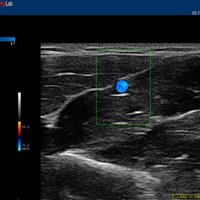

12”-Full-Touchscreen Farbdoppler

Das MyLab™One steht für das revolutionäre „Arm-held“ Hochleistungs-Ultraschallsystem mit 12”-Full-Touchscreen. Aufgrund seines geringen Gewichts und der Tragbarkeit kann es auch ohne Arbeitsfläche verwendet werden. Eine einzelne Person kann dieses Gerät aufgrund seiner einzigartigen Funktionen allein und selbstständig bedienen.

Der intuitive Touchscreen bietet dem Benutzer schnellen und einfachen Zugang zu allen Steuerungsfunktionen. Mit der beeindruckenden Bildqualität und einem kompakten Design wird MyLab™One zur idealen Ultraschalllösung am Point-of-Care.

• Features: Farb/Doppler, Nadelführung, SW/B-Bild